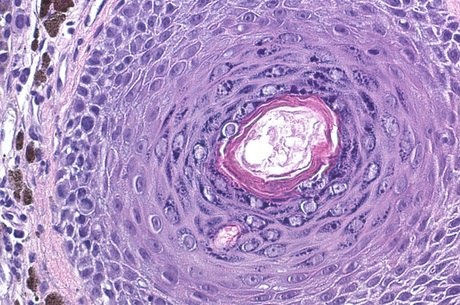

Hidden Beauty: Exploring the Aesthetics of Medical Science.